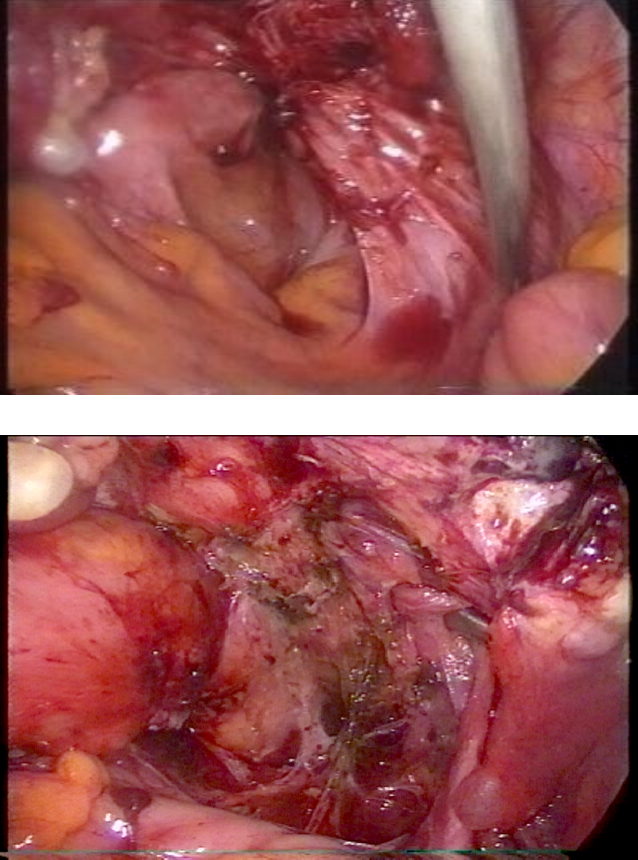

Endometriosis